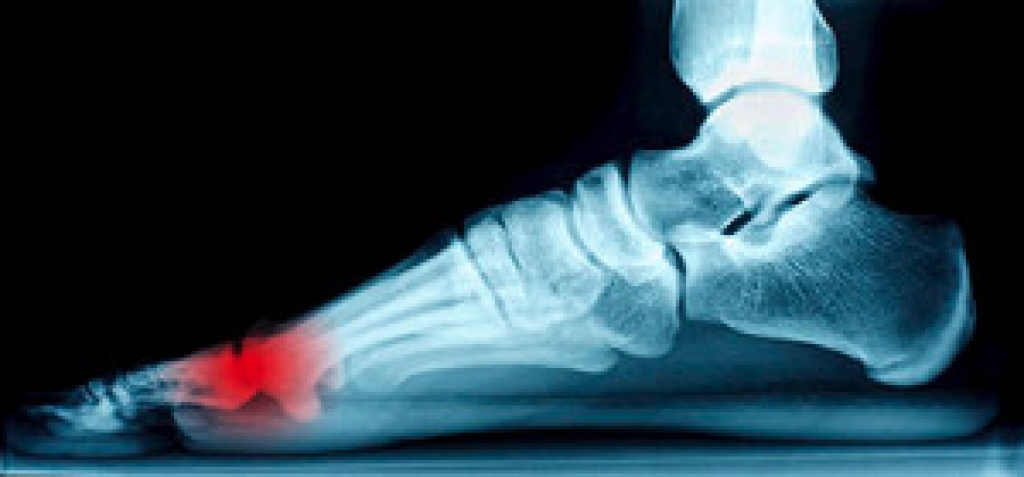

Someone would seek the care of a podiatrist if they have suffered a foot injury or have common foot ailments such as heal spurs, bunions, arch problems, deformities, ingrown toenails, corns, foot and ankle problems, etc.

A podiatrist will treat the problematic areas of the feet, ankle or lower leg by prescribing the following:

- Physical therapy

- Drugs

- Orthotic inserts or soles

- Surgery on lower extremity fractures

A common podiatric procedure a podiatrist will use is a scanner or force plate which will allow the podiatrist to know the designs of orthotics. Patients are then told to follow a series of tasks to complete the treatment. The computer will scan the foot a see which areas show weight distribution and pressure points. The podiatrist will read the analysis and then determine which treatment plans are available.